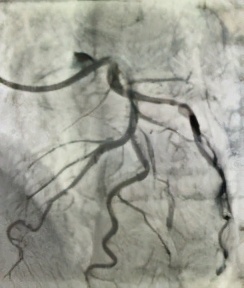

杨某,男,68岁,“因反复胸闷一周”入院,入院后行冠脉造影术,透视下见冠脉严重弥漫性钙化,右冠中段闭塞;前降支近段到中段严重95-99%弥漫性狭窄,病变处发出粗大第二对角支,第二对角支开口到近段95-99%弥漫性狭窄,属于真性分叉病变伴严重钙化;回旋支近段80%弥漫性狭窄,发出丰富侧枝循环供应右冠。患者命悬一线!刘杰主任率先对前降支分叉病变预处理后,在OCT指导下完成了分叉支架手术(culottes),术后OCT结果显示分叉支架贴壁良好,术后患者胸闷立即改善。

钙化及分支血管

最小管腔

术前

术后